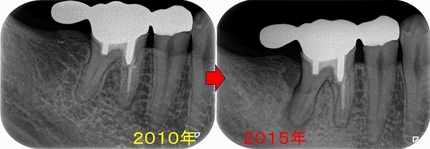

歯牙移植とヘミセクションから10年

先日昔治療させてもらった患者さんが詰め物が取れたということで来院されました。

この部位は

以前、延長ブリッジが入っていた歯

ふと、最近延長ブリッジ見なくなったなと思います。

(昔からあまりやらない方が良い治療だとは思っていましたが)

特に問題無かった歯なので、このままにしておいたのですが、

5年後

遠心根に透過像が出てきており、歯茎からは膿が出てきていました。

日本の根管治療の約6割には問題があるというはあながち間違いではないと思います。

とりあえず根管治療をして治すことにしましたが、

近心根にはパフォーレーション 手付かずの遠心根には破折線が見られ、

患者さんにどうします!?遠心根はまず残せない、近心根は残すことが出来るがパフォーレーションの位置的に長く持たない可能性がある。

不思議なんですが、遠心根は根管治療していないにも関わらず折れてきている。

イメージ的に根管治療を行い中を削って歯を弱体化させている近心根が折れるならまだ分かるのですが・・・

患者さんと話し合い、近心根はヘミセクションをして残す 遠心根は抜歯

右下7の所には親知らずの移植と計画をしました。

この後遠心根抜歯

口腔外科で移植をしてもらい、移植歯の根管治療を行い

ある程度咬めるように治させてもらいました。

今年になり患者さんが詰め物が外れたとのことで来院

10年経過して、そこまで悪い感じはありません。

患者さんにも「先生にそんなに持たないかもしれないよと言われていましたが10年持っています。意外と持つものですね!」と言われましたが、

ホント最初の延長ブリッジの方がかなり良い条件でしたが、折れてしまった。

パフォレーション+分割抜歯、移植した歯という条件の悪いケースで10年経過している。。。

たぶん、私がそんなに持たないかも!?と言った事でかばって咬むようにしているのが

今の状況を作っていると思いますが、ホント術者がどんなに頑張っても咬む力(歯ぎしり含め)で歯は必ず悪くなってきてしまいます。

こういうケースを見ると、患者さんの協力なしで歯を長く持たせることは難しいと感じます。

今回のケースは詰め物のやり替えだけ行えば、またしばらく使うことは可能でしょうd(^。^)